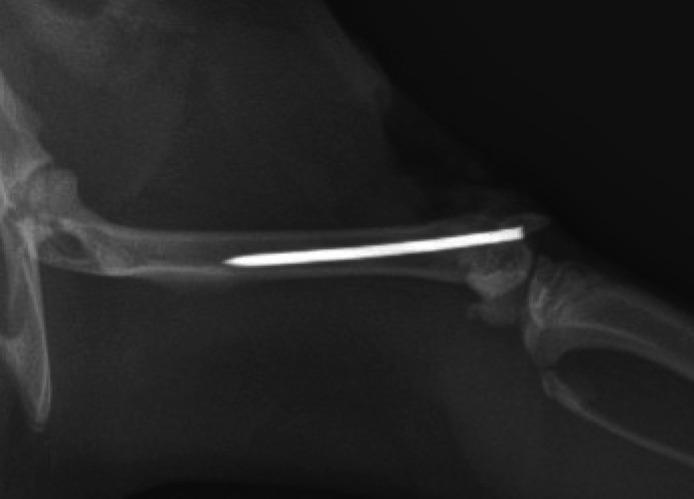

The cell toxicity of different concentrations of EDTA dissolved in NS (EDTA-NS) was assessed by Cell Counting Kit-8 (CCK-8). Various concentrations of EDTA-NS irrigation solution were compared in three female Sprague-Dawley rat models: 1) a skin defect; 2) a bone exposed; and 3) a wound with an intra-articular implant. All three models were contaminated with or . EDTA was dissolved at a concentration of 0 (as control), 0.1, 0.5, 1, 2, 5, 10, 50, and 100 mM in sterile NS. Samples were collected from the wounds and cultured. The bacterial culture-positive rate (colony formation) and infection rate (pus formation) of each treatment group were compared after irrigation and debridement.

Cell viability intervened below 10 mM concentrations of EDTA-NS showed no cytotoxicity. Concentrations of 1, 2, and 5 mM EDTA-NS had lower rates of infection and positive cultures for and compared with other concentrations in the skin defect model. For the bone exposed model, 0.5, 1, and 2 mM EDTA-NS had lower rates of infection and positive cultures. For intra-articular implant models 10 and 50 mM, EDTA-NS had the lowest rates of infection and positive cultures.

方法

通过细胞计数试剂盒-8(CCK-8)评估溶解于NS(EDTA-NS)中的不同浓度EDTA的细胞毒性。在三种雌性斯普拉格-道利大鼠模型中比较了不同浓度的EDTA-NS冲洗液:1)皮肤缺损;2)骨外露;3)有关节内植入物的伤口。所有三种模型均被 或 污染。将EDTA以0(作为对照)、0.1、0.5、1、2、5、10、50和100 mM的浓度溶解于无菌NS中。从伤口采集样本并进行培养。比较冲洗和清创后各治疗组的细菌培养阳性率(菌落形成)和感染率(脓液形成)。

结果

在10 mM以下浓度的EDTA-NS干预下,细胞活力未显示细胞毒性。在皮肤缺损模型中,1、2和5 mM的EDTA-NS浓度与其他浓度相比, 和 的感染率和阳性培养率较低。对于骨外露模型,0.5、1和2 mM的EDTA-NS感染率和阳性培养率较低。对于关节内植入物模型,10和50 mM的EDTA-NS感染率和阳性培养率最低。